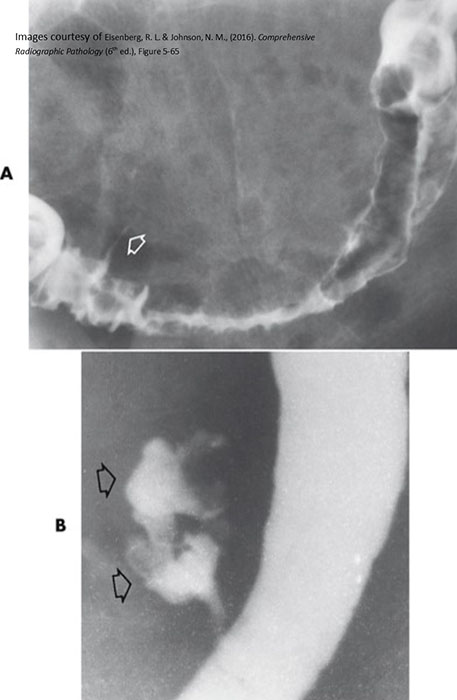

What is intussusception?

Telescoping of a proximal bowel segment into a distal segment, causing obstruction.

Why is intussusception dangerous?

It compresses the mesentery, cutting off blood supply and causing necrosis.

Where does intussusception most commonly occur in children?

At the ileocecal valve.

Sudden severe abdominal pain, distension, vomiting, and a palpable right-sided mass.

What is 'red currant jelly' stool?

Stool mixed with blood and mucus, classic for pediatric intussusception.

Air or water-soluble contrast enema.